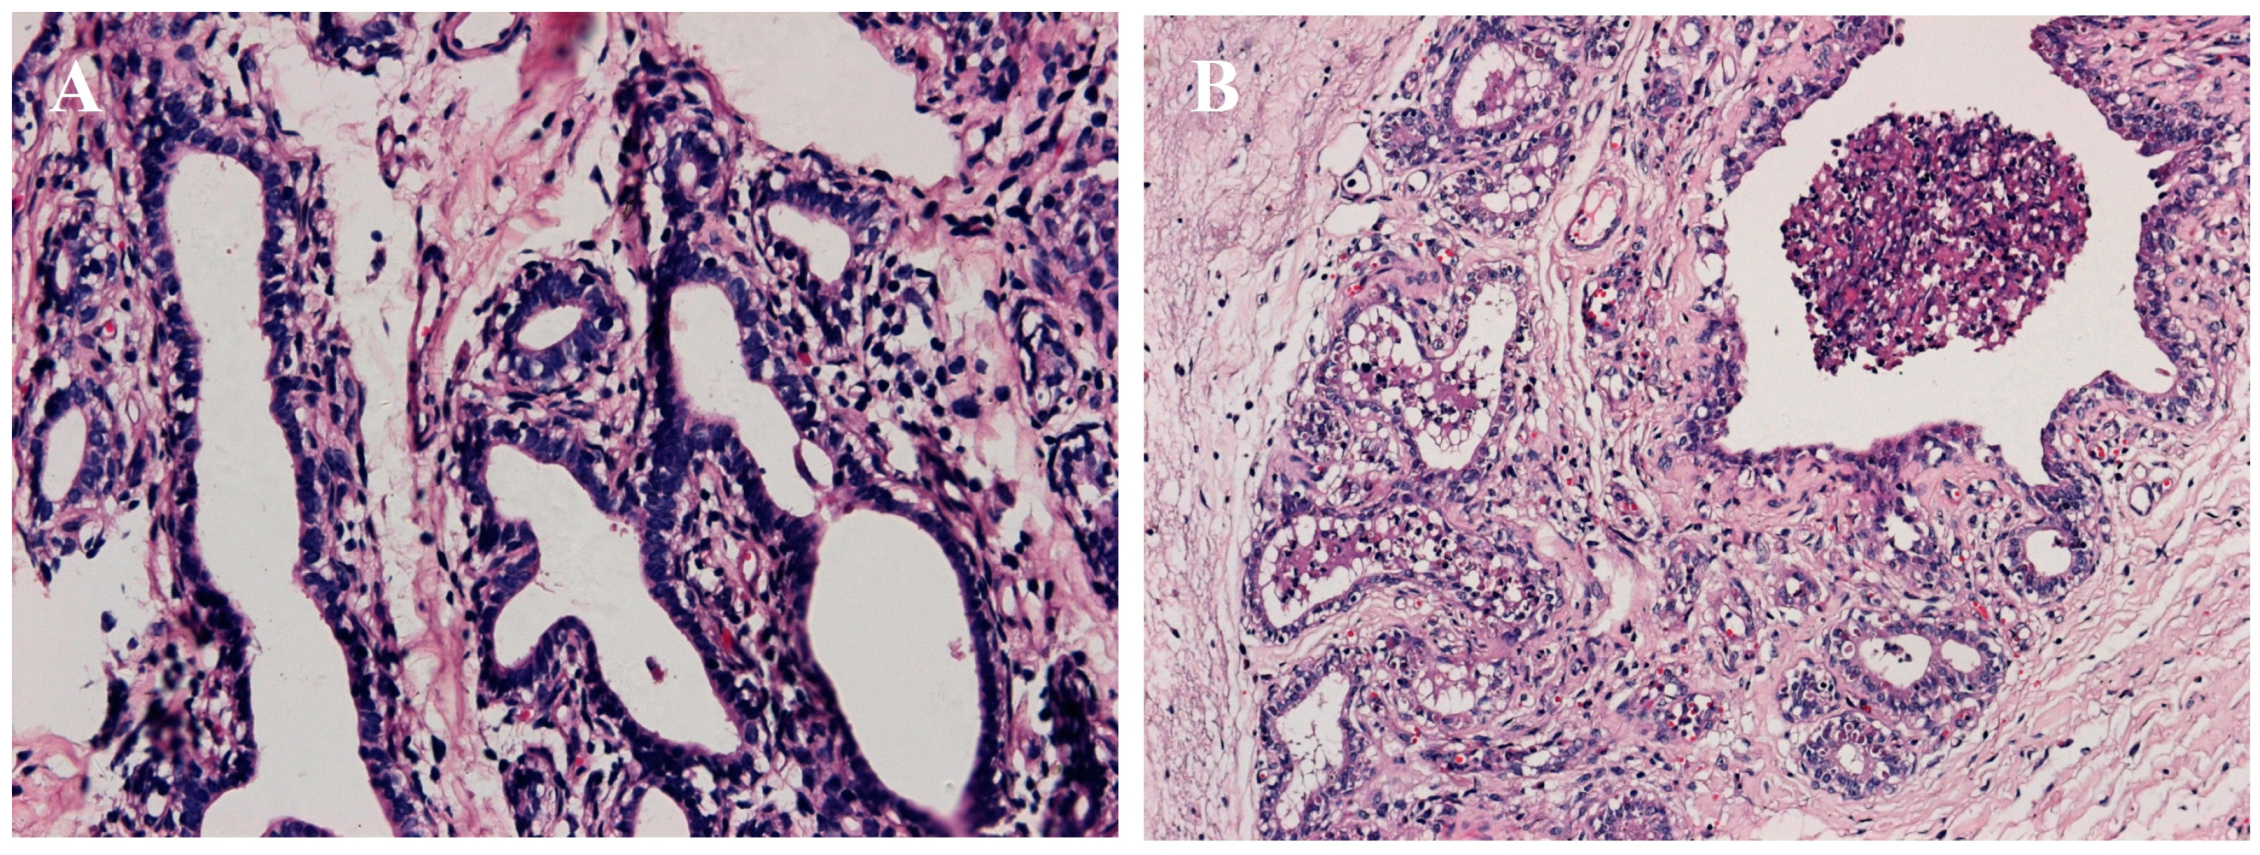

4.4. Histologic Examination